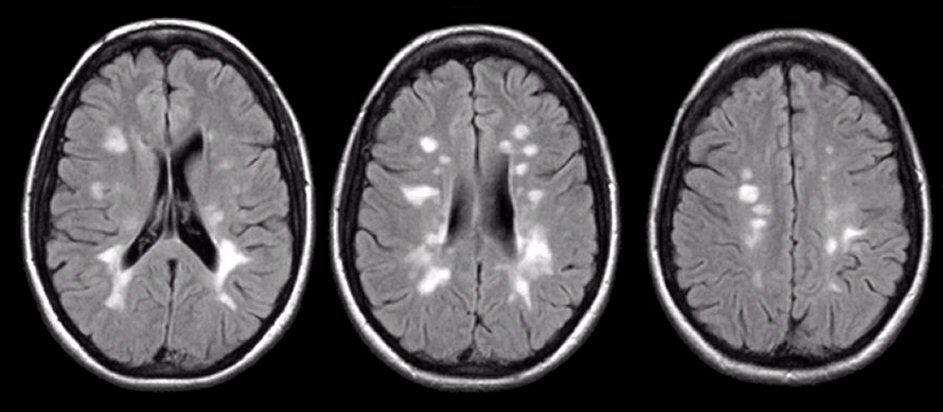

| Multiple sclerosis plaque | Well-defined low-attenuation (or subtle) lesions, often periventricular; better seen on MRI, but CT may show hypodense plaques without mass effect. |